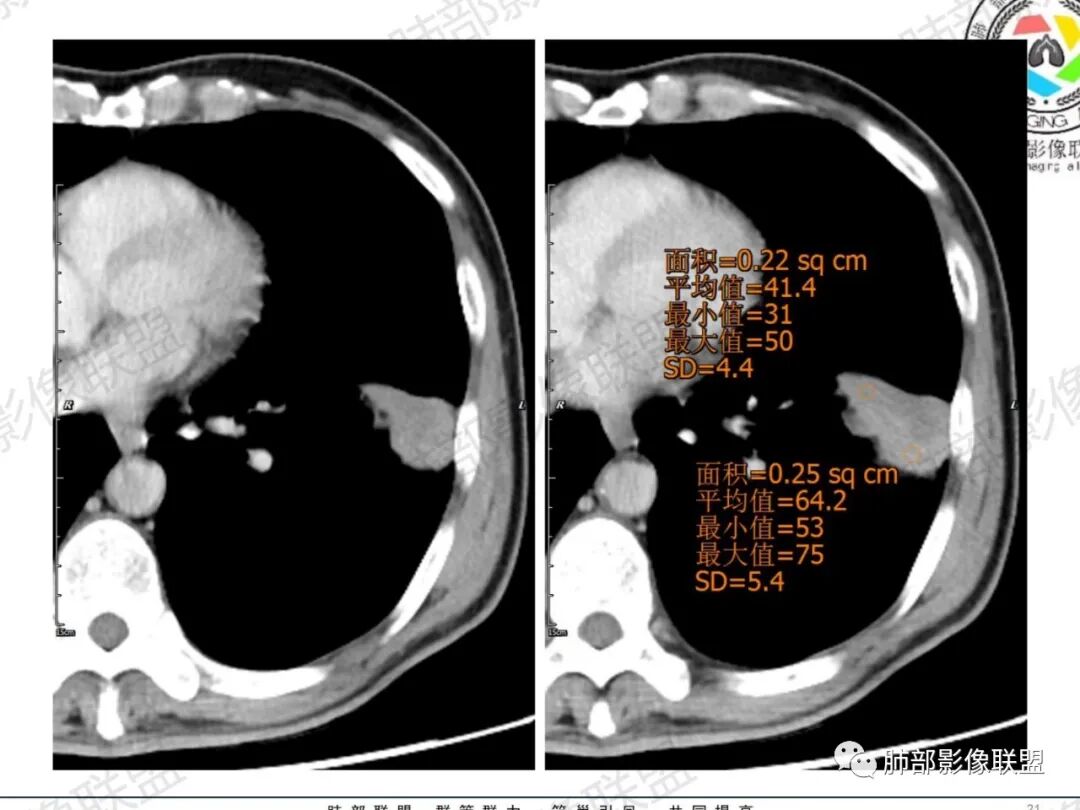

琦遇:恶性没有问题,肺气肿底子、病灶分叶、少许毛刺、叶间胸膜凹陷、部分边缘可见清晰的GGO、胸膜牵拉凹陷、局部胸水、近端支气管截断、部分支气管被推移、占位效应明显、强化特点为不均匀强化、内部有少许沼泽样低强化区,强化部分轻中强化为主、余肺可见转移性结节、左肺上叶似为囊腔型腺癌一枚,肿瘤标志物提示非小、神经内分泌,综合分析考虑大神泌、腺癌、腺鳞癌、鳞癌  同时左肺上叶囊腔型腺癌  肺转移

傅昌瑜:中老年男性,肺气肿背景,右胸背疼痛1周。CEA、NSE、CYFRA—211升高。左上肺混合磨玻璃结节,内见较多空泡和扩张支气管。左下肺胸膜下肿块,边缘较光滑,深分叶,似有血管进入,与支气管关系不清,内见不均匀强化,见沼泽地样坏死,有胸膜栽赃。另两肺多发圆形小结节。考虑恶性并肺内转移,多原发可能性大,左上肺腺癌,左下肺病理难以判断,小细胞癌?鳞癌?

蓝天白云:中年男性,肺气肿背景,左肺下叶肿块,边缘膨隆,有分叶,内有湖泊样坏死,有轻中度强化,局部胸膜栽赃,收缩力不强,周围见肺气肿征象。左肺上叶混合磨玻璃影,边界清楚,考虑都是恶性,左上肺iac,左下肺腺鳞癌,或大细胞肺癌可能。两肺多发结节,考虑转移

LCNEC最常见的影像特征包括:(1)肿块发生部位:周围型肺癌为主,少数发生于肺中央。(2)肿块大小及形态。因肿瘤细胞生长迅速常形成较大肿块,因此其体积一般较大,直径常在3~10cm范围内,病灶常为不规则形软组织肿块。(3)肿块边界。多数学者报道大多数肿块边界清晰,边缘呈分叶状,毛刺征及“胸膜凹陷征”少见,认为与该病对周围组织浸润较轻及较少产生纤维瘢痕组织牵拉有关联。(4)肿块密度、强化特点及代谢情况。据文献报道,该类肿瘤因体积较大CT上常见软组织肿块,且多数密度不均匀,内见囊变坏死区,增强后呈轻或中度不均匀强化(可见强化者占75.7%),认为其强化特点与其内部肉眼可见坏死灶和肿瘤较大直径有关。(5)伴随症状及远处转移。该病恶性程度高,侵袭性强,常侵犯邻近结构,如胸膜、心包、邻近骨质或纵隔内组织等,易出现纵隔淋巴结转移,部分发生肺内及远处转移,少数早期可出现广泛远处转移。